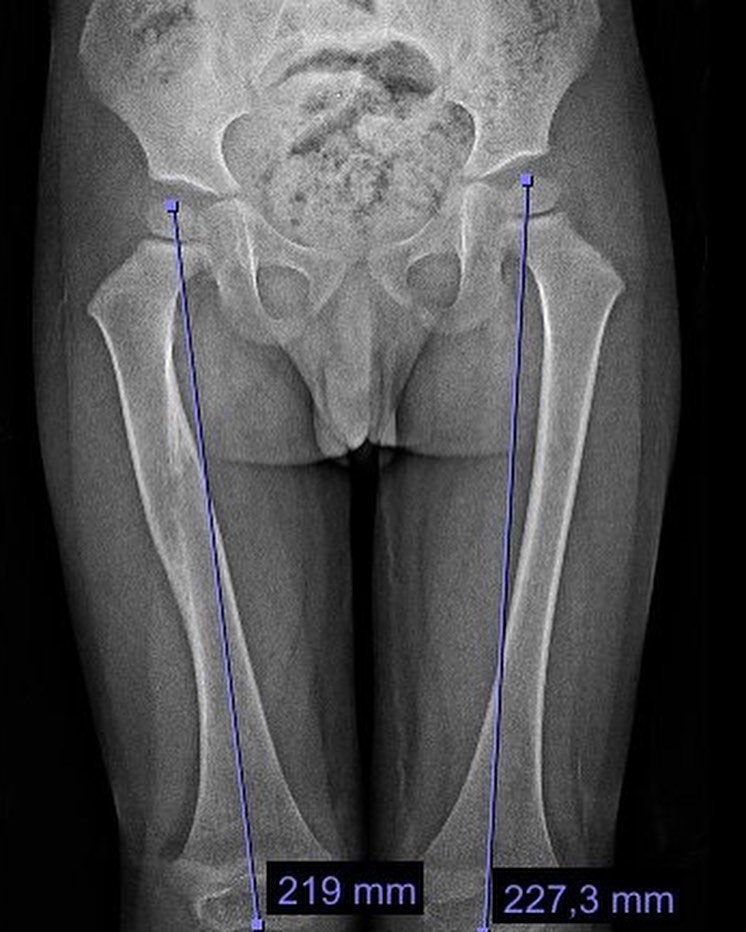

Fractura de fémur

El año pasado mi pacientito Dylan se fracturó el fémur, realizamos tratamiento conservador y ahora está al 💯 Vino a consulta y recibí este delicioso regalo, ¡muchas gracias Dylan!

El año pasado mi pacientito Dylan se fracturó el fémur, realizamos tratamiento conservador y ahora está al 💯 Vino a consulta y recibí este delicioso regalo, ¡muchas gracias Dylan!